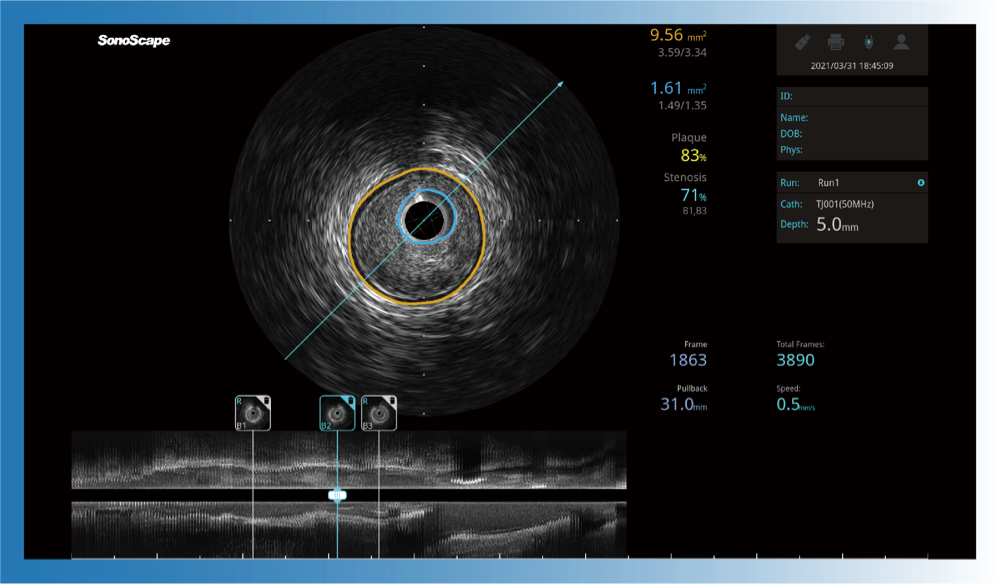

对比传统IVUS导管成像,16877太阳集团宽频IVUS图像的近场支架梁显影更细腻,远场中膜外血管仍清晰可辨,兼顾远中近,兼顾分辨力与穿透深度

治疗前后两次测量录像对比

简化疗效评估

一键智能描迹,自动测量斑块负荷、面积狭窄率等指标,准确率高于90%